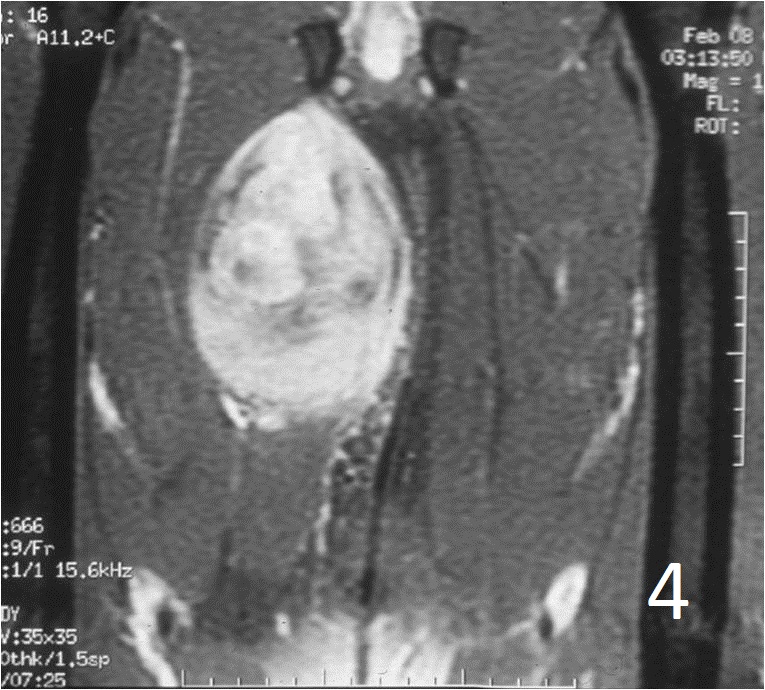

• Well defined heterogenous mass on T2W (Fig. 4, 9)

• Necrosis and hemorrhage are common, especially in high grade tumors

• On gadolinium, viable areas of tumor enhance, while areas of significant necrosis and hemorrhage do not enhance (Fig. 6).

Fig. 2-4: An MRI of the thigh shows a mass in the medial compartment that is isointense to muscle on T1W images (Fig. 2) and heterogeneous on T2W (Fig. 3). Sagittal T1W post contrast with gadolinium demonstrates enhancement of the tumor (Fig. 4).